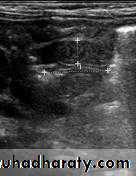

Pyloric stenosis is relatively common and has a male predilection (M:F ~ 4:1), and is more commonly seen in Caucasians 4. It typically occurs between the 4-8 weeks of life. There may be a positive family history. Incidence of hypertrophic pyloric stenosis is approximately 2-5 per 1,000 births per year in most white populations,Hypertrophic pyloric stenosis refers to idiopathic thickening of gastric pyloric musculature which then results in progressive gastric outlet obstruction

In a normal situation, the pyloric muscle thickness (diameter of a single muscular wall on a transverse image) should normally be less than 3 mm (most accurate 3) and the length (longitudinal measurement) should not exceed 15 mm.